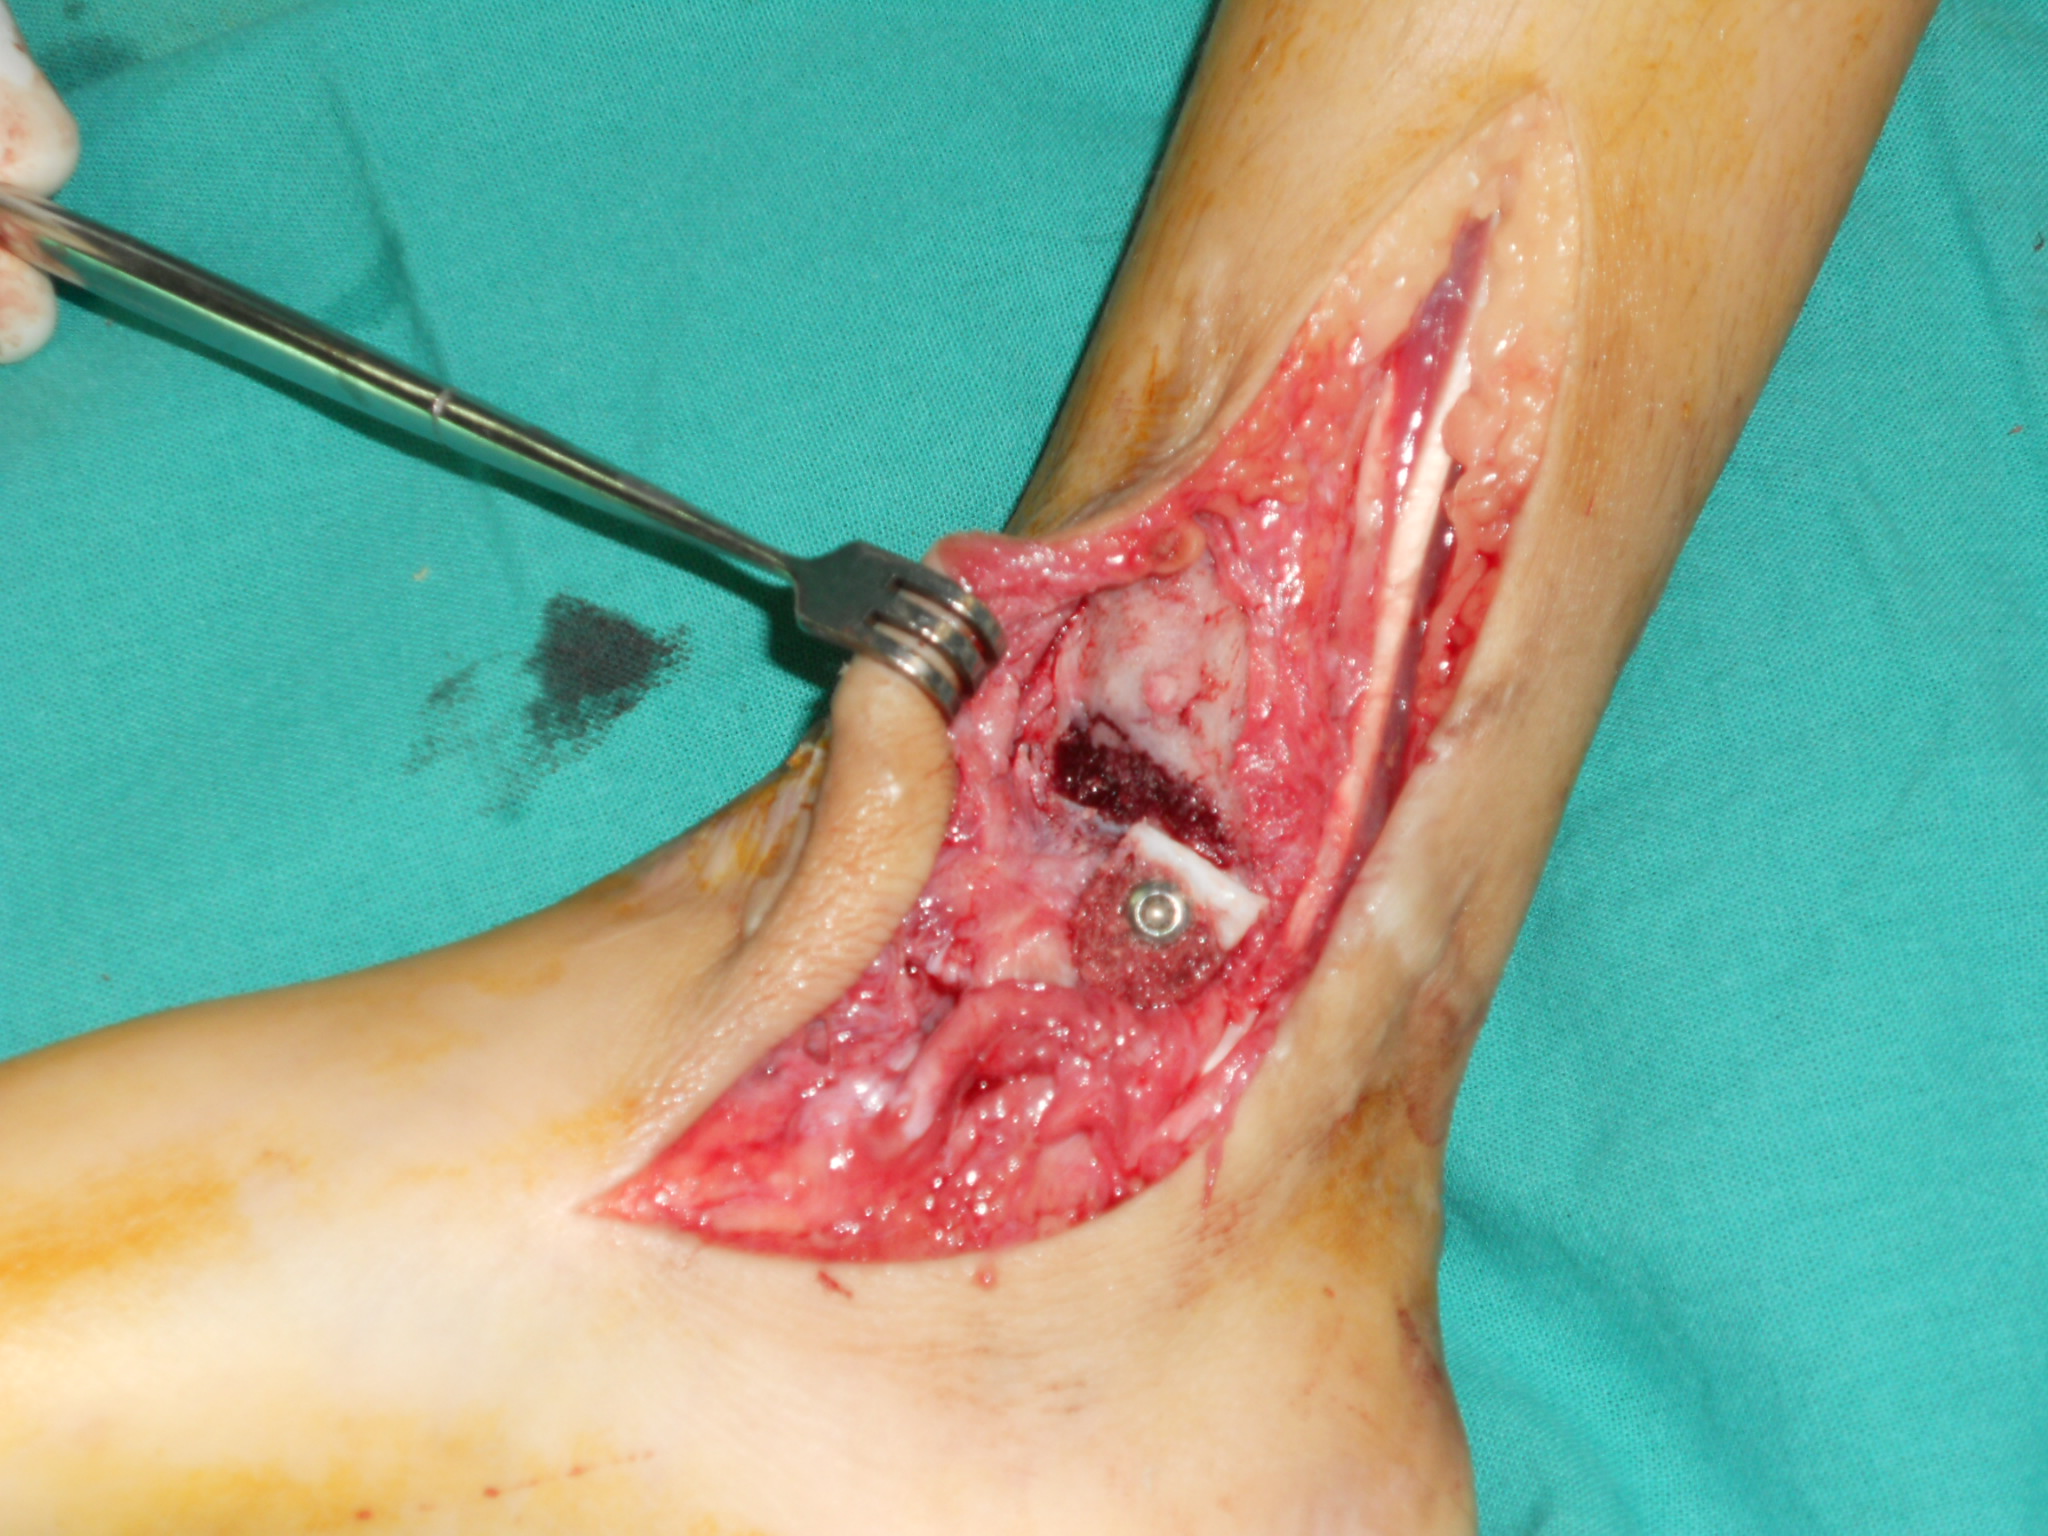

Fracturas fisarias Salter-Harris VI de tobillo y pie. [Salter-Harris VI fractures of the foot and ankle.]